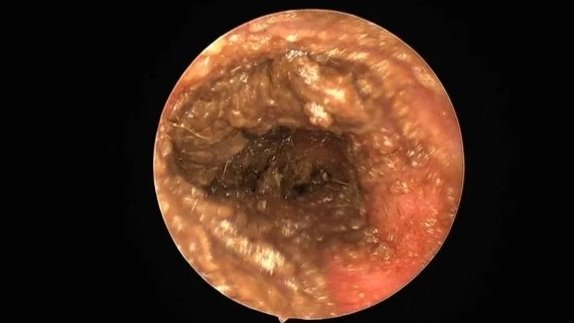

View of the inside of a dog's ear canal with a chronic bacterial infection and purulent debris.

Stinky, purulent ears with rods - you can smell them in the waiting room.

These ears need a thorough deep ear clean under anaesthesia to break down biofilm, remove exudate, obtain deep samples for culture and sensitivity, and evaluate the tympanic membrane.